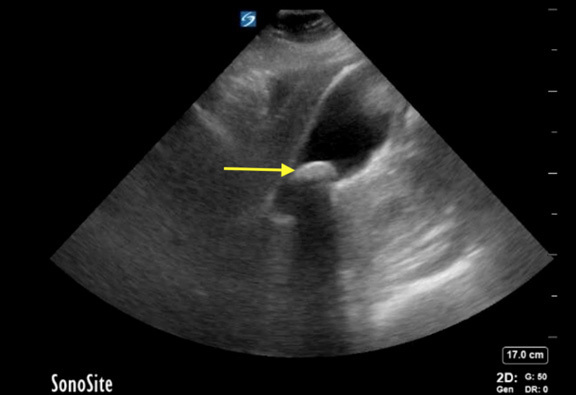

Figure 1. Cholelithiasis in the Gallbladder |

Presence of cholelithiasis within the gallbladder (yellow arrow). Note the posterior acoustic shadowing of the stones. |

Image courtesy of Daniel Migliaccio, MD, FPD, FAAEM. |